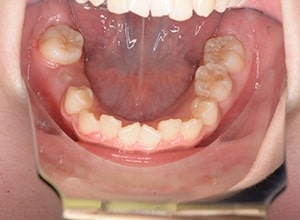

| 口腔内所見 | over jet 3.5mm,over bite4.0mm、下顎正中右側偏位2.0mm、大臼歯関係は左側Ⅰ級であったが、右下6は右下E早期喪失のため近心傾斜しておりⅢ級の臼歯関係となっていた。また上下顎前歯は軽度の叢生を呈していた。 |

| パノラマ所見 | 右下5は右下6近心傾斜により萌出部位不足が認められた。上下顎8歯胚が確認できた。 |

| 批評・予后 | 右下5及び7の萌出前に右下6を整直させることによって、右下5の自然萌出が可能となり正常咬合への咬合誘導が行えたと思う。 |